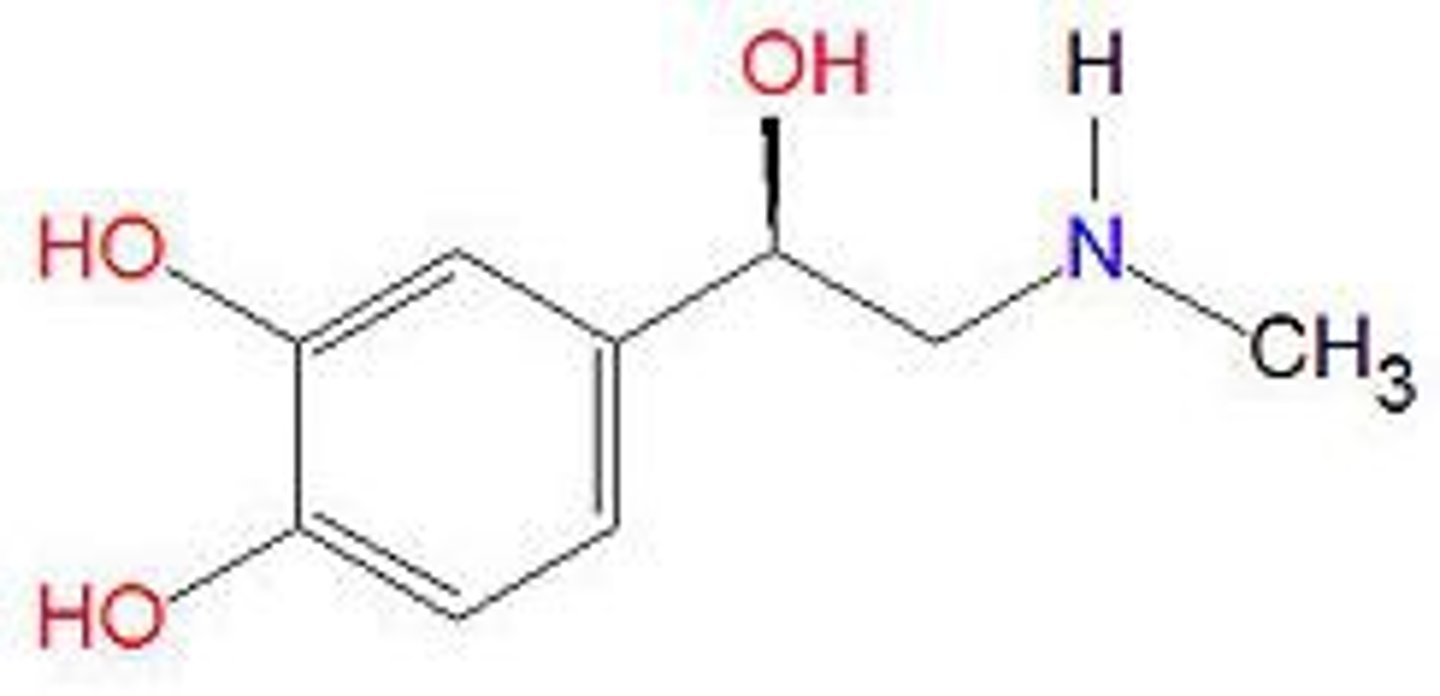

Norepinephrine (NE)

neurotransmitter that regulates brain arousal and other functions like mood, memory, hunger, and sleep

Adrenaline

a hormone secreted by the adrenal glands, especially in conditions of stress, increasing rates of blood circulation, breathing, and carbohydrate metabolism and preparing muscles for exertion